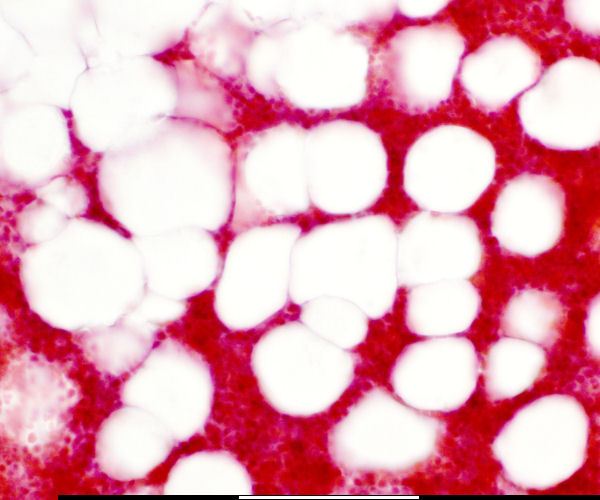

back Bone marrow